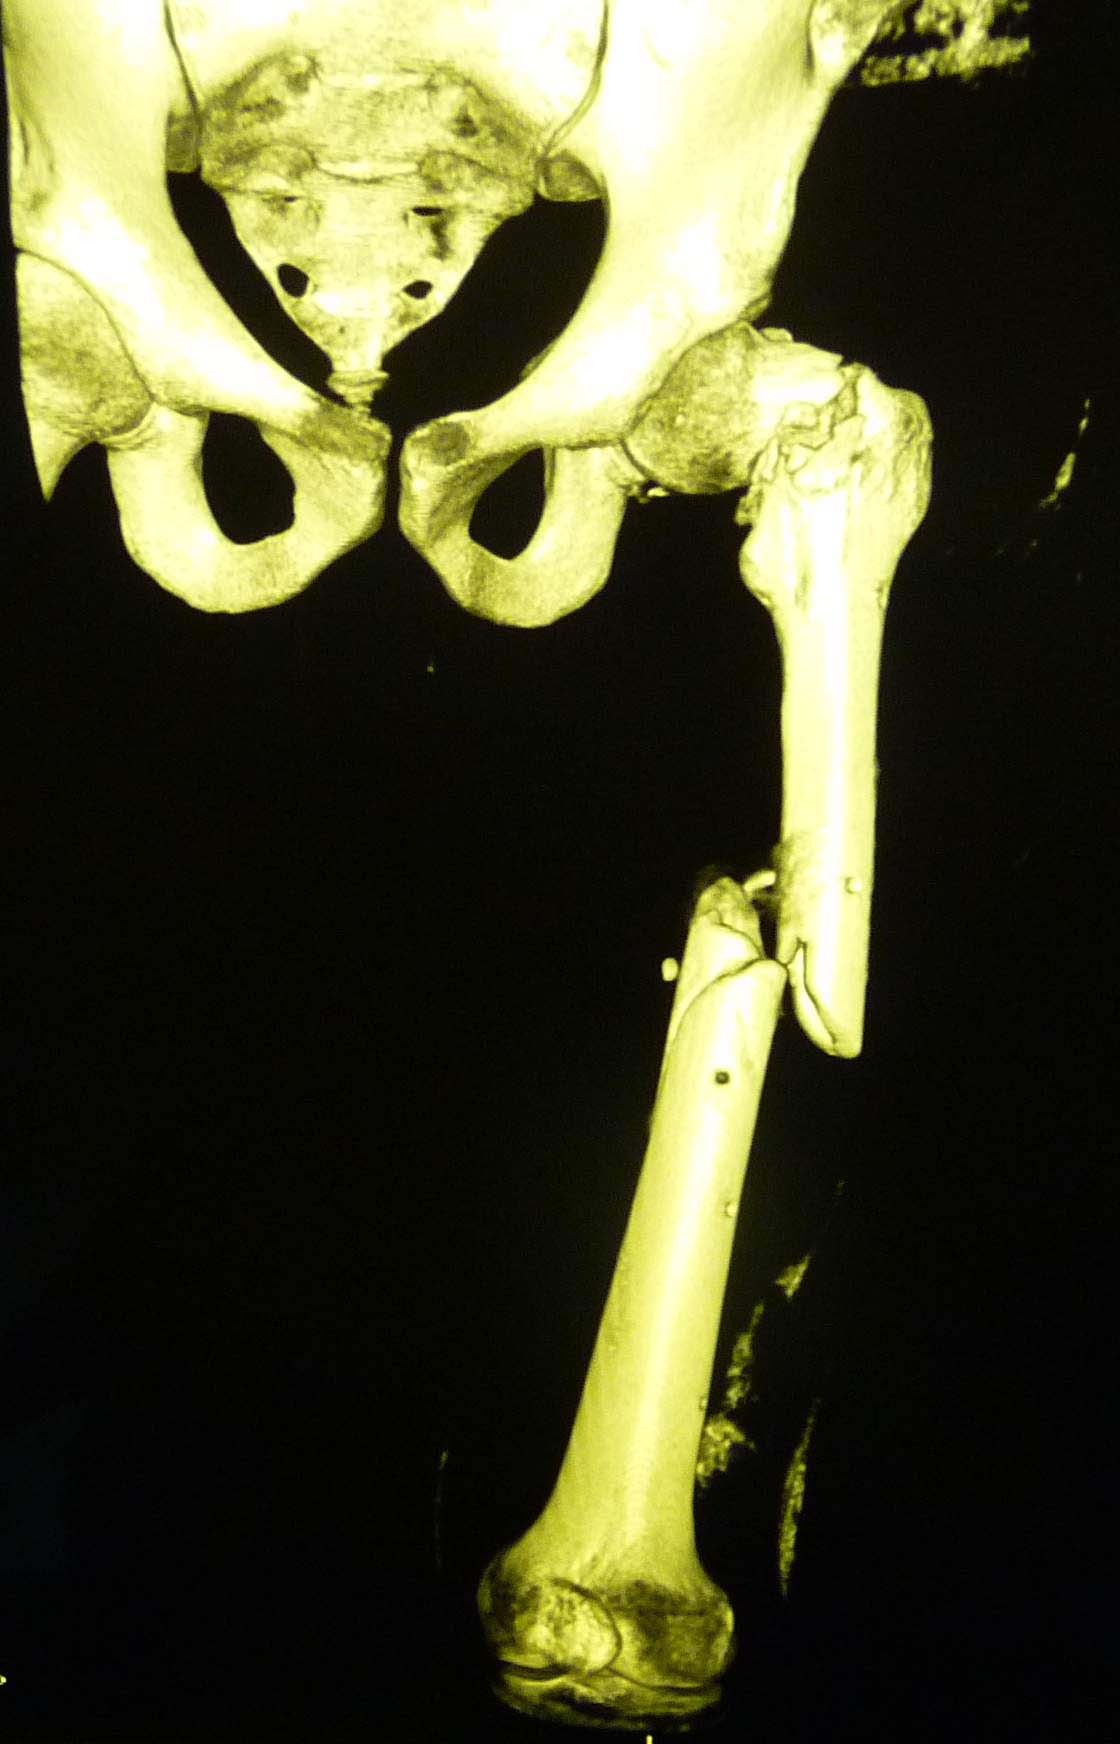

Добрый вечер уважаемые коллеги. На днях оперировал б-ного 36лет, с переломом шейки и диафиза бедра, травма высокоэнергетическая, ЭОП нет, оперируем под рентген контролем закрытым способом,т.е зона перелома не открывается, правда, получается долго. В общем в ходе операции все было хорошо и рентген контроль тоже, осталось только докрутить до конца винты, и после операции контроль.рентген ни делал, устал, и был уверен, что все нормально. На второй день у б-ного резко начали подниматься печеночные ферменты(АЛТ,АСТ)до 5-6 раз, ИФА-отр, гепатологи хотят перевести, и сделал Р-графию перед переводом. Осталcz варус, верхний винт упирается в сустав, что делать пока не знаю, может быть? винт немножко отвинтить и ждать! И тут же обратиться к Вам уважаемые коллеги! С уважением Абдурашид.

В лечении ипсилатеральных переломов шейки и диафиза бедренной кости приоритетное значение имеет точная репозиция и надёжная фиксация перелома шейки бедренной кости. Именно сращение шейки бедренной кости имеет превалирующее значение в конечном исходе лечения таких переломов. С моей точки зрения фиксация перелома шейки бедренной кости только двумя блокирующими винтами при использовании реконструктивного стержня не является оптимальным выбором. Помимо этого, как правило, возникают трудности технического плана при репозиции перелома шейки бедренной кости из-за невозможности управлять вертельной частью в связи с остающейся ротационной нестабильностью в месте перелома диафиза после введения стержня. Мне представляется, что оптимальным способом лечения таких переломов является ретроградный остеосинтез перелома диафиза с последующим остеосинтезом перелома шейки бедренной кости тремя канюлированными винтами. Что касается вашего случая. Безусловно, так оставлять нельзя. Больному 36 лет. После стабилизации состояния больного мы бы удалили реконструктивный стержень, выполнили ретроградный остеосинтез. Однако в данном случае остеосинтез шейки бедренной кости предпочтительнее выполнить пластинкой DHS, учитывая наличие отверстий в подвертельной области и дефектов кости в шейке и головке от проксимальных блокирующих винтов.

У Синтеза специально для таких двойных переломов есть латеральный бедренный гвоздь, позволяющий увеличить расстояние между гвоздем и линией перелома шейки за счет смещения кнаружи точки введения гвоздя. Во вложении - трехлетней давности пример: остеосинтез выполнен через полтора месяца после травмы, вполне удалась закрытая репозиция проксимального перелома. Единственный непонятный для меня момент такой операции - невозможность динамизации диафизарного перелома без удаления фиксаторов из головки. В представленном случае шейка срослась быстро, а вот диафиз - только после удаления верхних винтов и установки винта в динамическое отверстие в подвертельной области.

Добрый день коллеги! судя по представленным ренгенограммам имеет место базальный перелом шейки бедренной кости и спиральный клин с промежуточным фрагментом в области диафиза. имеется ряд проблем:

1)неадекватная репозиция и несоответсвующий фиксатор, при введении которого и появился варус.

1)Удаление имеющейся конструкции, реостеосинтез длинной версией GN,PFN, латеральным бедренным гвоздем. обязательным условием проксимального блокирования является сохранение спиц в шейке до окончания блокирорвания.

2)Ретроградный БИОС и винты в шейку

3)Накостный остеосинтез с применением длинной пластины с винтом DHS+антиротационный винт в шейку бедра.Применение двух пластин может быть проблематичным технически и создать нежелательную зону напряжения в в/3 диафиза вплоть до периимплантного перелома в последующем.